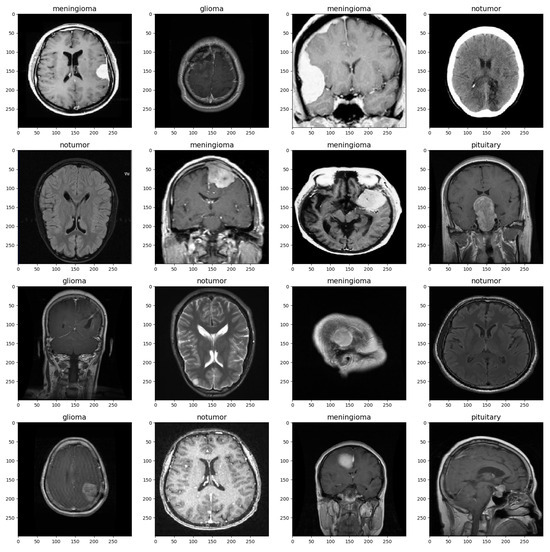

The Brain Tumor MRI dataset used in this research is a publicly available dataset containing a total of 7023 MRI images: 5712 training images and 1311 testing images [11]. The data are grouped into four distinct categories: pituitary, meningioma, glioma, and no tumor. Specifically, the testing subset comprises 300 pituitary images, 306 meningioma images, 300 glioma images, and 405 no-tumor images, while the training subset includes 1457 pituitary images, 1339 meningioma images, 1321 glioma images, and 1595 no-tumor images.

The MRI images were split into training and validation sets with a split ratio of 50%, ensuring stratification based on class labels to maintain class balance. Before being used for training, the images were preprocessed and augmented to ensure the model could handle a diverse range of images, such as those with low brightness and various orientations [12]. Table 1 shows the set values for the parameters. The images were rescaled to a value of 1/255, and brightness was set to a range from 0.8 to 1. Rotation, zoom, shift, and flip shear were adjusted as depicted in the table. These parameter settings increase the diversity of the training data and improve the model’s ability to generalize to a wide range of MRI images [13]. Figure 1 provides a visualization of the brain tumor image dataset.

Figure 1.

Brain MRI Data Sample.